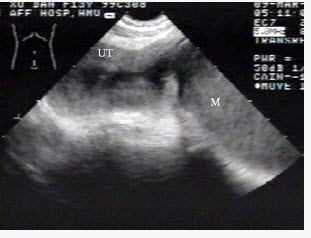

女性,62岁,1周前疑诊为宫颈癌。超声检查如图,最可能的诊断是()

[单选题]女性,62岁,1周前疑诊为宫颈癌。超声检查如图,最可能的诊断是()A .子宫肌瘤B .宫腔积液并感染C .子宫内膜癌D .子宫内膜炎E .正常声像图